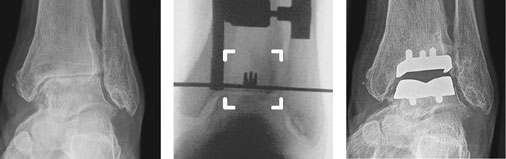

Von links nach rechts:

Sprunggelenk vor Implantation der Sprunggelenkprothese. Der Gelenkspalt ist

aufgehoben, der Knorpel ist abgerieben.

Anvisieren der Prothesenlage wie über Kimme und Korn mit dem Spezialinstrumentarium.

Durch moderne Präzisionsinstrumentarien wird die Sprunggelenksprothese millimetergenau implantiert.